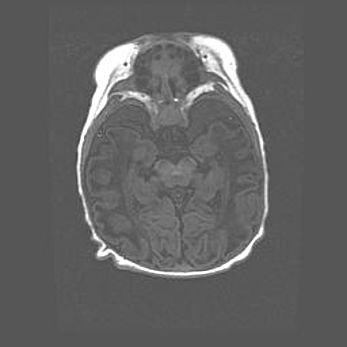

Подострая гематома правой гемисферы мозжечка.

Наружная гидроцефалия.

Возраст: 15 дней

Вес: 3100 г

Пол: женский

Окружность головы: 37 см

Срок гестации: 35-36 недель

При открытой наружной форме гидроцефалии у новорожденных расширяются и переполняются субарахноидные пространства.

Кровоизлияния в мозжечок имеют две клинико-анатомические формы: полушарные гематомы и кровоизлияния в червь.

К появлению этой патологии может привести: повреждения головного мозга, возникающие в результате асфиксии и гипоксии плода при беременности, или травмы во время родов. Редко гематома мозжечка может быть результатом первичной коагулопатии и сосудистой мальформации, диссеминированном внутрисосудистом свертывании, изоиммунной тромбоцитопении.